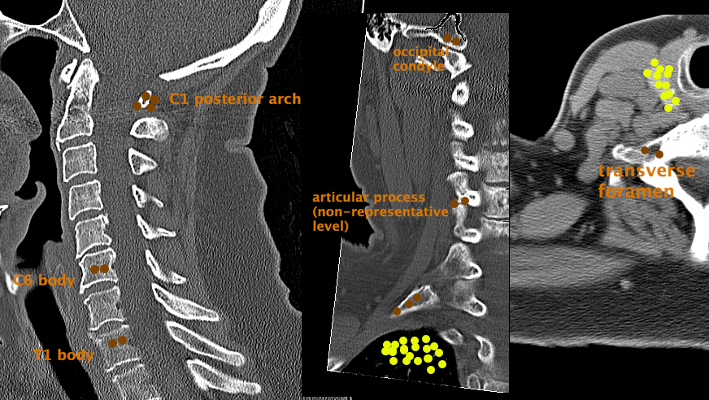

CT Cervical Spine

Legend:

Brown - Fracture

Yellow - Mass

Number of dots is proportionate to frequency

C1fx C6fx T1fx OccipitalFx ArticFx TransverseFx ThyroidMass LungMass ribfx